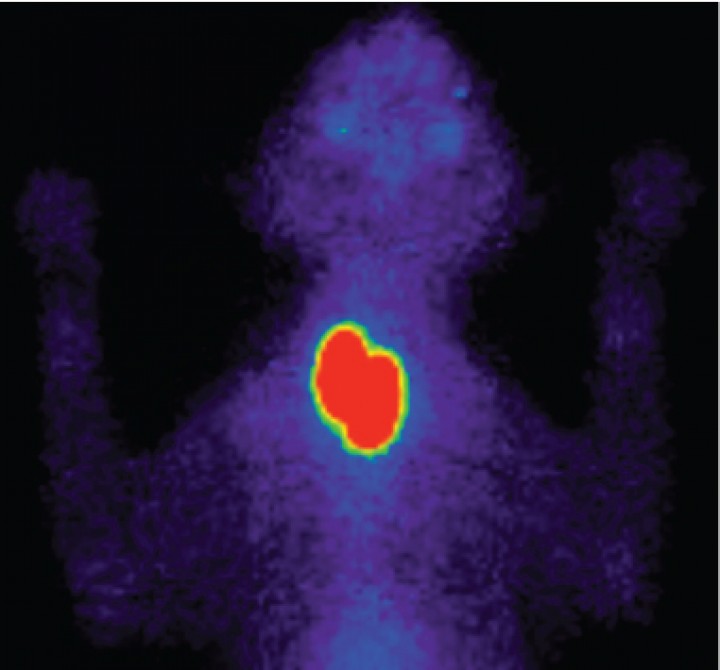

- Para calcular las dosis de radiofármaco (dosis personalizadas) en el tratamiento con yodo radiactivo (131I). El objetivo del tratamiento con 131I en gatos hipertiroideos es la destrucción de todo tejido hiperfuncional respetando el tejido tiroideo sano. La gammagrafía nos aporta datos del volumen y del porcentaje de captación de tecnecio[ Peterson ME, Guterl JN, Rishniw M, Broome MR. Evaluation of quantitative thyroid scintigraphy for diagnosis and staging of disease severity in cats with hyperthyroidism: comparison of the percent thyroidal uptake of pertechnetate to thyroid-to-salivary ratio and thyroid-to-background ratios. Vet Radiol Ultrasound. 2016; 57(4):427-440. [PubMed] ] del tejido hiperfuncional, lo cual nos permite ajustar las dosis en cada caso para obtener un mayor porcentaje de curación, minimizando el riesgo de producir hipotiroidismo iatrogénico (Fig. 5).[ Xifra MP, Peterson ME. Hipertiroidismo felino. En: Pérez MD, Arenas C, Melian C (eds): Manual de Endocrinología en Pequeños Animales. 2ª ed. Barcelona, España. Multimédica; 2018:143-192. , Peterson ME, Xifra MP, Broome MR. Treatment of hyperthyroidism: radioiodine. En: Feldman EC, Fracassi F, Peterson ME (eds). Feline Endocrinology. Milan, Italia: Edra; 2019:227-254. , Xifra Rubio P, Serrano Garcia, SI, Peterson ME. Hipertiroidismo felino: Diagnóstico y evolución de la enfermedad mediante gammagrafía y tratamiento con yodo radiactivo (131I). Rev Cient Esp Med Intern Peq Anim 2018;2:25-31. , Lucy JM, Peterson ME, Randolph JF et al. Efficacy of low-dose (2 mCi) versus standard-dose (4 mCi) radioiodine treatment for cats with mild-to-moderate hyperthyroidism. J Vet Intern Med. 2017; 31:326-334. [PubMed] , Peterson ME, Guterl JN, Nichols R, Rishniw M. Evaluation of serum thyroid-stimulating hormone concentration as a diagnostic test for hyperthyroidism in cats. J Vet Intern Med. 2015; 29:1327-1334. [PubMed] ]

<p>Gammagrafías tiroideas, pretratamiento y postratamiento con <sup>131</sup>I, de un gato hipertiroideo. (<strong>A</strong>) Gammagrafía pretratamiento que muestra un patrón unilateral derecho con aumento de captación de <sup>99m</sup>Tc-pertecnetato (ratio T/S: 4,5). El paciente fue tratado con una dosis baja de <sup>131</sup>I (1,4 mCi), ajustada en base a los datos obtenidos en la gammagrafía previa. (<strong>B</strong>) Gammagrafía a los 6 meses postratamiento, que muestra el restablecimiento del eutiroidismo sin producir hipotiroidismo iatrogénico (ratio T/S: 1,2).</p>

Gammagrafías tiroideas, pretratamiento y postratamiento con 131I, de un gato hipertiroideo. (A) Gammagrafía pretratamiento que muestra un patrón unilateral derecho con aumento de captación de 99mTc-pertecnetato (ratio T/S: 4,5). El paciente fue tratado con una dosis baja de 131I (1,4 mCi), ajustada en base a los datos obtenidos en la gammagrafía previa. (B) Gammagrafía a los 6 meses postratamiento, que muestra el restablecimiento del eutiroidismo sin producir hipotiroidismo iatrogénico (ratio T/S: 1,2).

- Para valorar la evolución en gatos hipertiroideos tratados con cirugía o yodo radiactivo. La realización de gammagrafías tiroideas postratamiento nos permite confirmar el éxito de los tratamientos realizados (eliminación de la totalidad del tejido hiperfuncional y existencia de tejido remanente sano).[ Xifra MP, Peterson ME. Hipertiroidismo felino. En: Pérez MD, Arenas C, Melian C (eds): Manual de Endocrinología en Pequeños Animales. 2ª ed. Barcelona, España. Multimédica; 2018:143-192. , Peterson ME, Xifra MP, Broome MR. Treatment of hyperthyroidism: radioiodine. En: Feldman EC, Fracassi F, Peterson ME (eds). Feline Endocrinology. Milan, Italia: Edra; 2019:227-254. , Xifra Rubio P, Serrano Garcia, SI, Peterson ME. Hipertiroidismo felino: Diagnóstico y evolución de la enfermedad mediante gammagrafía y tratamiento con yodo radiactivo (131I). Rev Cient Esp Med Intern Peq Anim 2018;2:25-31. ]